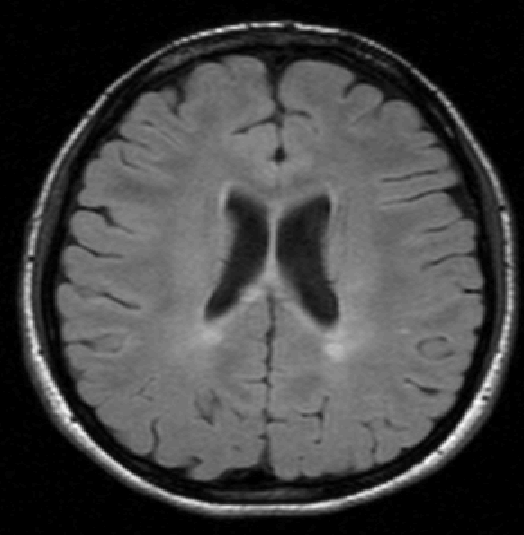

We use images from three different studies (see Fig. 1 for examples of slices):

10 MS patients from the MS Lesion Challenge [11] scanned at the Children’s Hospital of Boston (CHB), scanned with T1, T2 and FLAIR at 0.50.50.5mm resolution.

2.

- 3.

Here again the differences between study populations influence the class priors. On average, the percentage of voxels that are lesions are 1.6%, 2.6% and 0.2% in CHB, RSS and UNC respectively. The differences between subjects also vary: these are relatively small for CHB and UNC, but very large for RSS. In RSS, the subject with the least lesion voxels has only 0.08%, while the patient with the most lesion voxels has 14.3%.

For the WML task, we used 10 features per channel: intensity, {intensity, gradient magnitude and Laplacian of Gaussian} each after convolution with a Gaussian kernel at scales mm3, resulting in 30 features in total. Each voxel is associated with a binary label, either non-WML or WML. An illustration of how the distributions are different in different sources is shown in Fig. 2 (bottom).